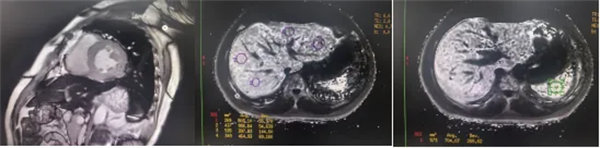

CMR是目前唯一能定量檢測(cè)組織鐵負(fù)荷的無(wú)創(chuàng)影像學(xué)手段,主要依賴其 T2*mapping技術(shù)測(cè)量的T2*弛豫時(shí)間(T2*值)間接量化組織鐵含量。當(dāng)CMR檢測(cè)出心肌T2*<20 ms時(shí),初步診斷心肌鐵過(guò)載,T2*值<10-15ms時(shí),提示心功能受損風(fēng)險(xiǎn)顯著增加。T2值越低,鐵沉積越嚴(yán)重。目前T2*mapping技術(shù)檢測(cè)T2*已作為臨床診斷肝臟、心肌鐵過(guò)載的首選無(wú)創(chuàng)檢查,也被用作隨訪工具評(píng)估疾病進(jìn)展和療效。

肝臟和脾臟信號(hào)改變 矢狀位梯度回波定位圖像可顯示肝臟和脾臟信號(hào)降低,提示肝脾鐵沉積,T2*>6.3及R2*>160/s表現(xiàn)中度鐵過(guò)載。